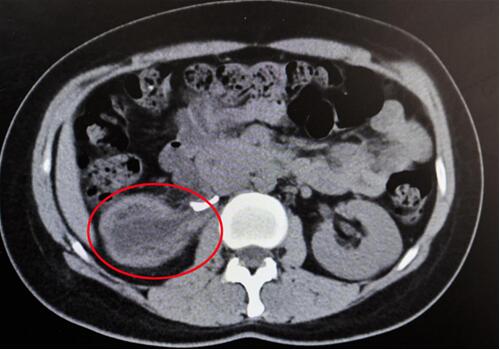

紅圈部分為手術前腎積水情況。院方供圖

“腎臟就像是一個皮球,因輸尿管完全閉鎖,里面的積水無法排出、越積越多,已經把表皮撐得很薄,在造影下甚至都看不清邊緣了!苯纳魅握f,“由于之前手術的粘連嚴重,手術難度頗大,腎臟能否保住是個未知數!